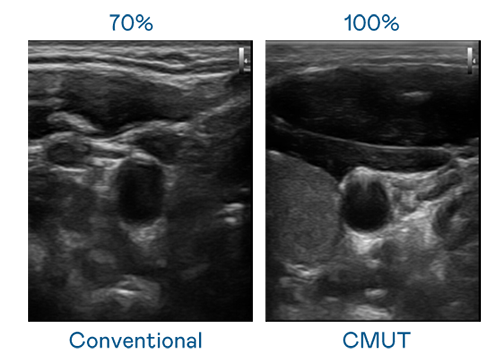

CMUT 技术是一种用电容式微机电元件来产生超音波讯号的技术。与传统 PZT 压电式技术相比,CMUT 频宽增加 30%,更宽频的超音波讯号让影像解析度大幅提升,是实现高影像品质医疗超音波扫描、促进精准医疗发展的关键技术。

超音波影像的解析度高低,首先取决于探头能发出的讯号频宽。AG视讯 CMUT 可提供高清晰的超音波讯号,提供高频宽、高灵敏度、影像纹理细节更高的超音波影像,协助医护人员缩短影像判读时间及利用精准的医疗影像进行诊断。